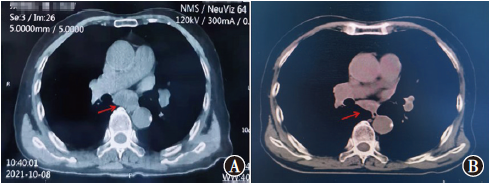

在非小细胞肺癌(NSCLC)的诸多驱动基因中,转染重排(RET)融合基因是一种新型突变基因,存在于1%~2%的NSCLC患者中。普拉替尼是一种RET抑制剂,用于靶向治疗RET融合阳性的NSCLC成人患者。现报道包头市中心医院收治的1例RET融合阳性NSCLC小肠转移老年患者的诊断过程、治疗方案及出现的不良反应,供临床参考。